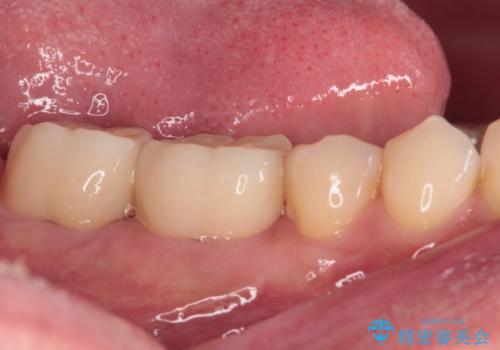

歯肉が腫れて出血する奥歯 歯周外科処置を用いたセラミック補綴治療

- 奥歯の間から出血するとのことで来院された患者様です。

口腔内は非常にきれいで、定期的に歯科医院でのクリーニングも行っているとのことでしたが、歯肉からの出血が一向に解決しない状態でした。

奥歯の歯間部の歯肉が炎症で赤黒くなっており、歯周ポケットを検査したところ、6-8mm(正常では3mm以下)であり、外科処置が適用となる状態でした。

まずは仮歯に置き換え、歯周ポケットを除去するための外科処置(歯肉弁根尖側移動術)を行い、治癒を待ってセラミッククラウンにて補綴治療を行うこととしました。

外科処置後は知覚過敏症状が酷くなることが多いのですが、術後は比較的落ち着いており、スムーズに処置を進めることができました。